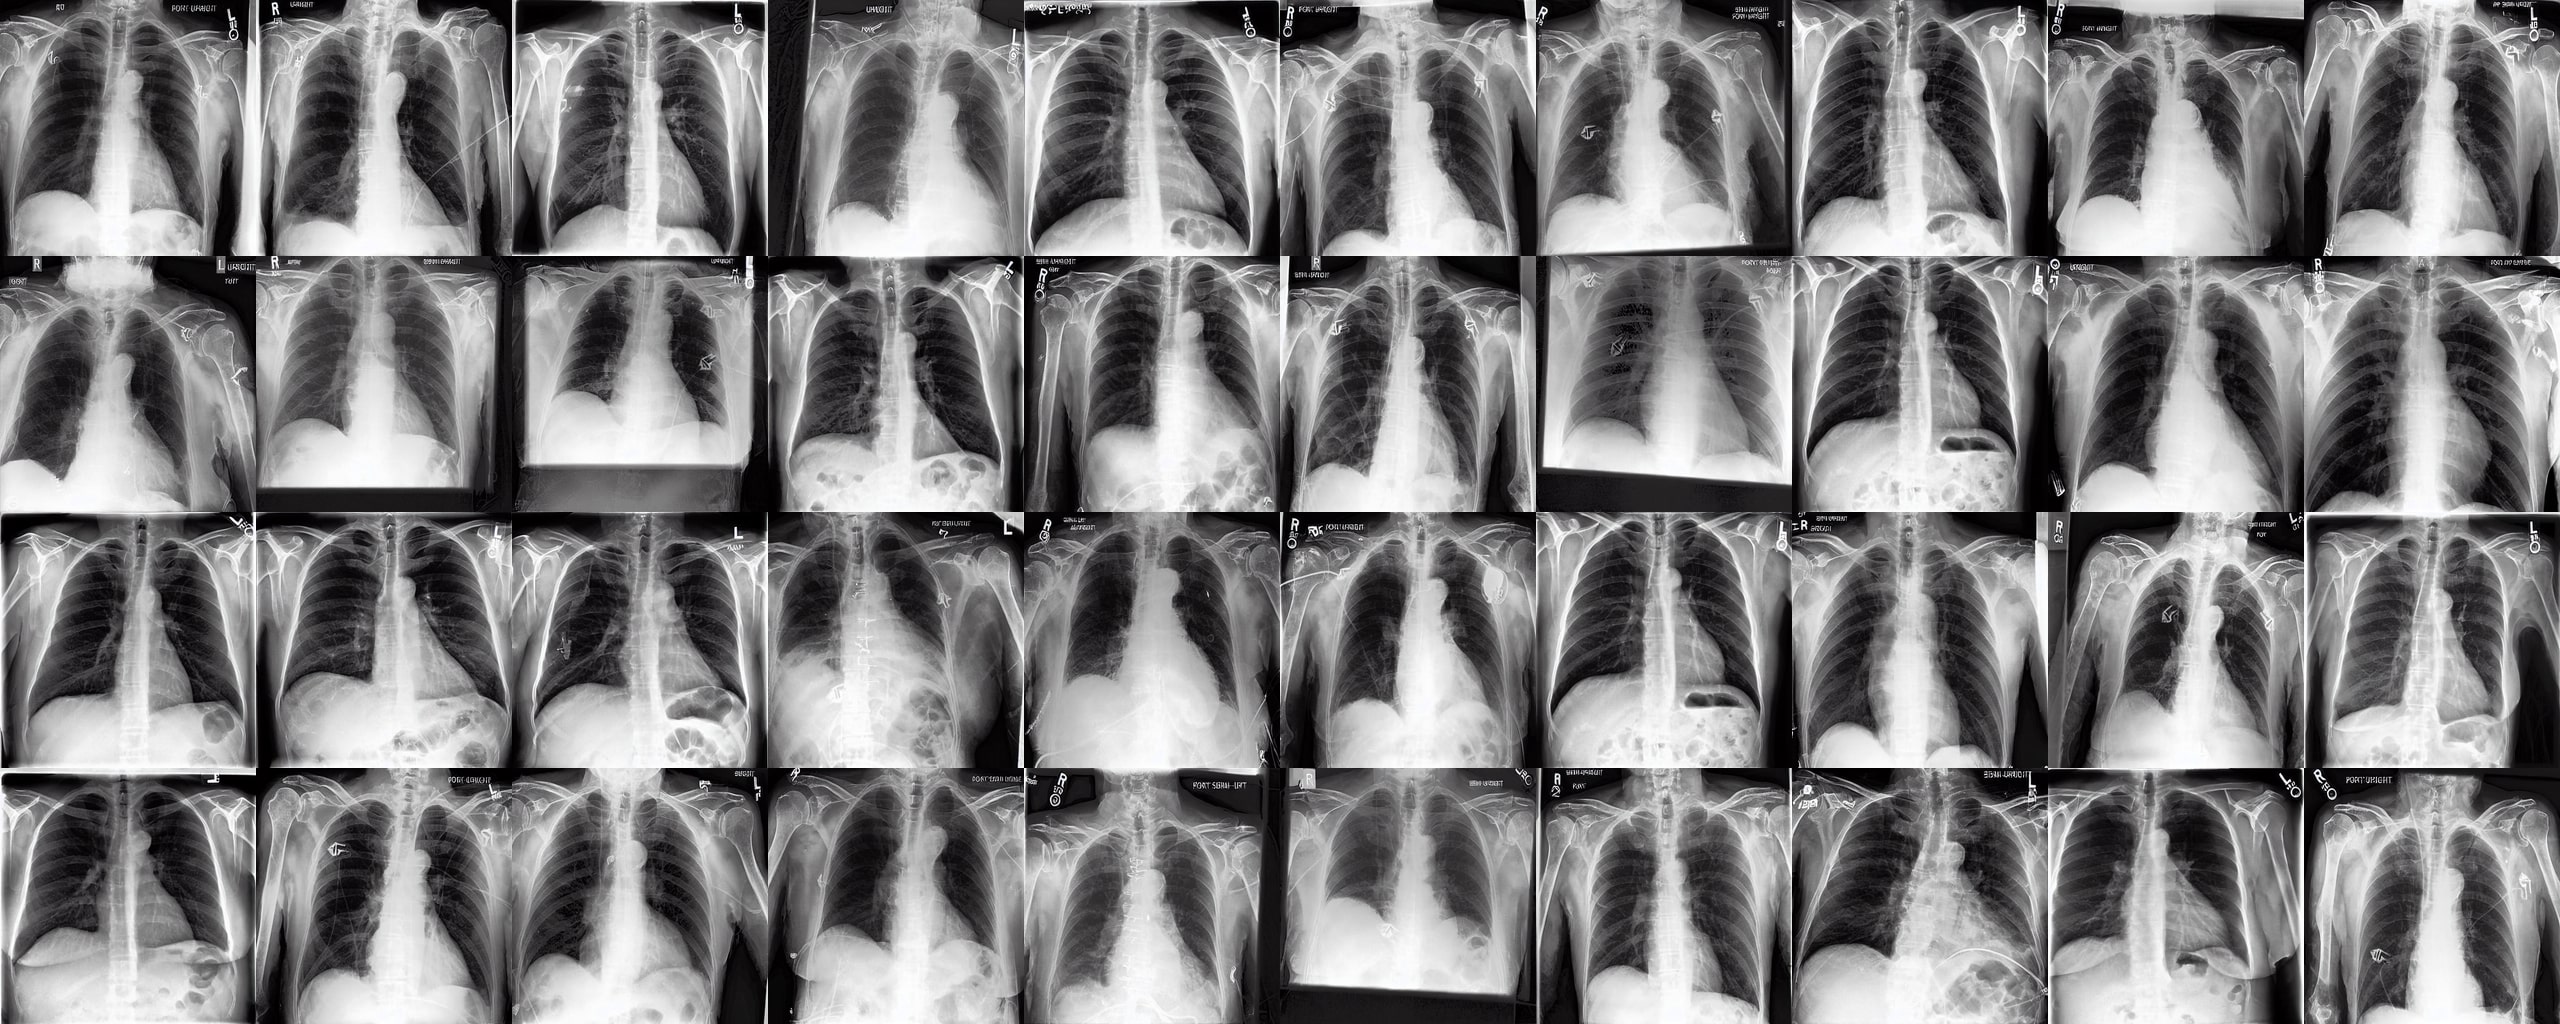

Chest X-rays We use the CheXpert dataset 10.1609/aaai.v33i01.3301590, which contains 170k training images. This dataset contains diversity in medical devices (such as chest tubes and wires), diseases (such as pneumonia and pleural-effusion) and anatomical details. We implement Rainbow on top of frozen parameters of a finetuned Stable Diffusion v1.5 (SD1.5) by previous work kumar2025prism for chest X-ray data. We generate 2D chest X-ray images based on text prompt conditions, e.g., "Chest X-ray showing Support Devices". In addition to the finetuned SD1.5, we include RadEdit perez2024radedit, a model trained from scratch on multiple chest radiology data such as CheXpert irvin2019chexpert, MIMIC-CXR johnson2019mimic, and NIH-CXR wang2017chestxray data for image editing tasks (more details at Appendix D.3), in the result comparison. Rainbow’s graph generator module includes , , and .

Chest X-rays Figure 4b quantifies generations by Rainbow and baselines using FID and VS. Rainbow achieves a higher VS, indicating greater diversity than the finetuned SD model, while also improving image quality with a lower FID score. Both Rainbow and SD outperform the RadEdit. Figure 6 provides a qualitative comparison, images are generated using the prompt "Chest X-ray showing support devices", where Rainbow generates a more diverse set of medical devices, such as pacemakers, in all generations, while baselines do not show any devices in some images. All models achieve similar CLIP scores of . Additional results including generations, Figure 22 and numeric results, Table 4, are outlined in Appendix E.

Chest X-rays To evaluate Rainbow on chest X-rays, we use FID and Vendi Score similar to the previous modalities. For feature extraction, we use a pre-trained DenseNet-121 [huang2017densely] model from the TorchXrayVision library [Cohen2022xrv], which is trained on multiple chest X-ray datasets such as CheXpert [irvin2019chexpert], NIH-CXR [wang2017chestxray], PadChest [bustos2020padchest], and MIMIC-CXR [johnson2019mimic]. The feature vectors used for calculating the metrics are extracted from the last layer (before the classifier head) with a dimensionality of 1024.

Chest X-rays We consider two chest X-ray baseline models. The first model is RadEdit [perez2024radedit], a latent diffusion model developed by Microsoft Health. This model is trained on 487,680 frontal view chest X-rays of multiple datasets such as MIMIC-CXR [johnson2019mimic], NIH-CXR [wang2017chestxray], and CheXpert [irvin2019chexpert]. The second baseline is a fine-tuned Stable Diffusion v1.5 model [kumar2025prism] on the CheXpert [irvin2019chexpert] dataset.